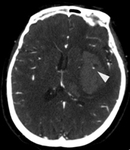

Sinal de ponto na angiotomografia (ponta da seta), indicando a presença de material de contraste hiperdenso no leito do hematoma na tomografia computadorizada (TC) após a injeção, correlacionou-se com maior risco de expansão subsequente do hematoma

Arquivos de casos pessoais do Foothills Medical Center; usados com permissão